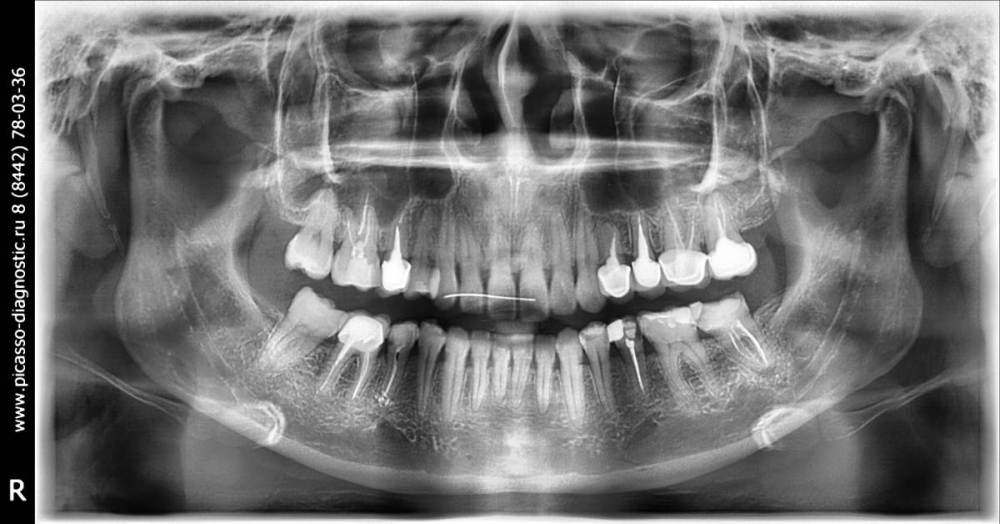

Katya88 Опубликовано 8 июля, 2021 Поделиться Опубликовано 8 июля, 2021 Болит второй день область верхней челюсти слева, там четыре мертвых зуба с вкладками и коронками. Какой то из них болит? Или возможно нижний с кариесом или пульпитом? Ссылка на комментарий

Doc Опубликовано 8 июля, 2021 Поделиться Опубликовано 8 июля, 2021 По одной ортопантомограмме, без осмотра сложно что-то толковое сказать, а гадать не хочется. Болеть может что угодно. Лучше обратиться к врачам лично и сделать КТ, а не ортопантомограмму. Ссылка на комментарий